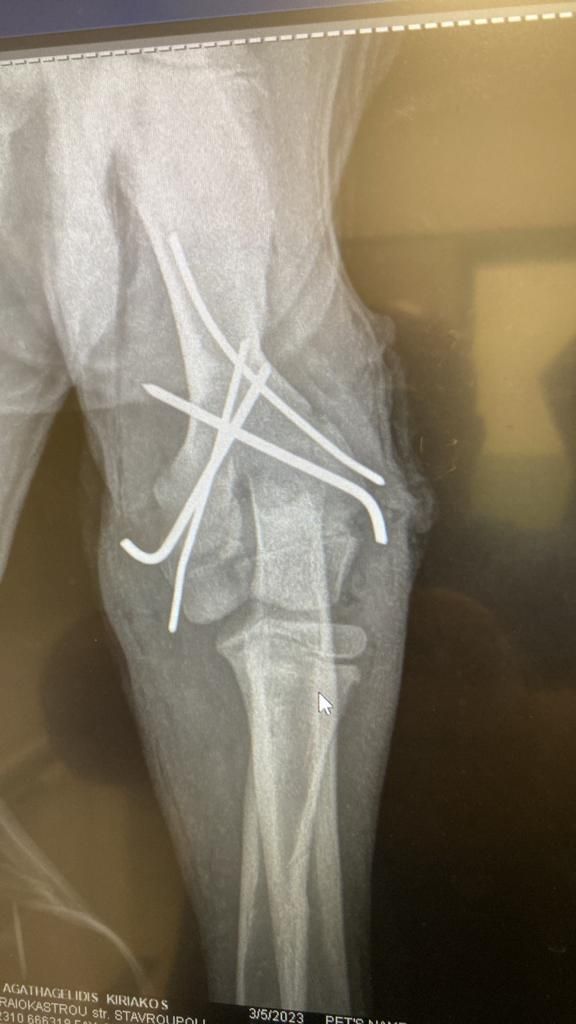

Aliki hat einen neuen Rüden in Obhut genommen. Dieser Hund, genannt Paok, ist ein Streuner, der in der Nähe ihrer Freundin Mareike lebte. Dort sind viele Häuser, viele Menschen, die ihn auch gefüttert haben. Eines Tages ist er aufgefunden worden, mit mehreren Knochenbrüchen. Die Gemeinde hat ihn aufgenommen und die Brüche operieren lassen.

Dann aber wurde er mal wieder sich selbst überlassen, und natürlich hat der Hund Schmerzen, so dass er den Gips aufgebissen hat. Aliki hat Mitleid mit dem armen Kerl und ihn erst mal aufgenommen. Sie wird versuchen, den Heilprozess in die richtige Richtung zu lenken, daher die Halskrause, die ein erneutes Aufbeißen verhindert. Aliki wird die Wunde täglich reinigen und so entzündungsfrei zu halten versuchen und Paok versorgen, bis er wieder zurück kann zu den Menschen, die ihn vorher bereits gefüttert haben. Anschließend wird sie sich darum kümmern, dass der Hund nun von der Straße ferngehalten wird. Aber erst heißt es einmal, dem armen Kerl die Daumen drücken und Aliki unterstützen, damit sie solche Hilfe Leistungen auch geben kann. 💙🥰

Update zu Paok 🐕🦺

Wir erinnern uns, dieser hübsche Streuner war in der Nähe von Mareike im März aufgegriffen worden, mit offenem Bruch, vermutlich ein Autounfall, er war von der Gemeinde operiert worden und dann zu Aliki gebracht worden. Der Tierarzt kam täglich, um den Nagel zu kontrollieren, dafür zu sorgen, dass die offene Wunde am linken Hinterlauf zuheilte. Dieser fröhliche, sehr zugewandte Hund nutzt leider sein Bein noch immer nicht, weshalb wir ihn dringend erneut vom Tierarzt untersuchen lassen wollen. Damit wir diese Kosten schultern können, suchen wir dringend Paten für Paok. Bitte helft uns! 🥰🐾💙